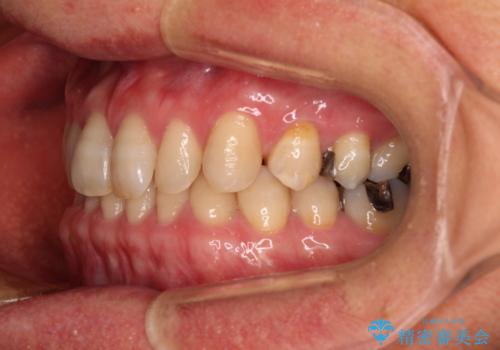

- 前歯のデコボコと隙間の空いた歯列を気にして来院された患者様です。

下顎前歯が隠れるほどのディープバイトにより、強い咬合力と突き上げで上顎歯列に隙間が空いている状態でした。

手前に傾斜している奥歯をワイヤー装置で立ち上がらせ、咬み合わせの高さを挙上することで突き上げを解消し、空隙歯列を改善していくこととしました。